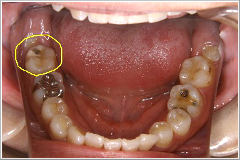

これは横向きに出てきた親知らずとその前の歯との間に食べ物が詰まり、取れなくなった為に奥の方まで炎症が広がり、結果的に前の歯を抜かなければならなくなった症例です。 この患者さんは「右下奥歯が動き出し、痛くて噛めなくなりました」といって来院されました。

ところが実際には、むし歯は前歯よりも奥歯の方がひどかったのです。歯を磨く事を止めてしまった結果がここに出てしまったのです。

その写真をここに載せますので見て下さい。